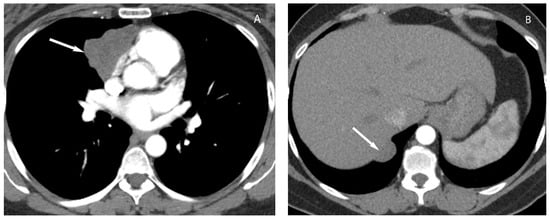

6. Lymphoma

8. Cystic Lesions